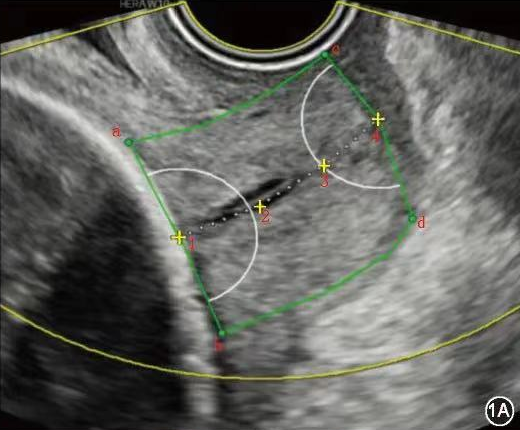

宫颈弹性成像技术是利用生物内部作用力如子宫动脉搏动及呼吸触发宫颈组织应变而获得宫颈各弹性参数,间接评估宫颈硬度,不受操作者影响。该技术是一种相对简便、直观、可重复操作的早产监测手段。应用二维灰阶超声联合E-cervix超声弹性成像,可为评估高危孕妇妊娠宫颈成熟度变化提供参考,对临床早期干预具有一定辅助价值。

临床上对于无症状高危孕妇一般通过经阴道指检判断宫颈软硬度对孕妇的早产概率进行预测,但该诊断方法尚无统一判定标准,仅凭检查者的主观意识进行诊断,极易影响检查结果。超声宫颈长度被认为是评估早产常用且有效的测量指标,尽管宫颈长度测量已成为临床实践的常见检查,仍有多数宫颈短小且无sPTB病史的孕妇在没有干预的情况下足月分娩,以及较多宫颈长度正常的孕妇发生早产。因为孕期宫颈胶原变化会先于宫颈缩短,而这些变化会让宫颈变软、托举力下降,传统方式(宫颈触诊、宫颈长度测量)难以捕捉。宫颈弹性成像技术有助于更早发现这种改变,并提供宫颈软硬程度的量化参考信息。